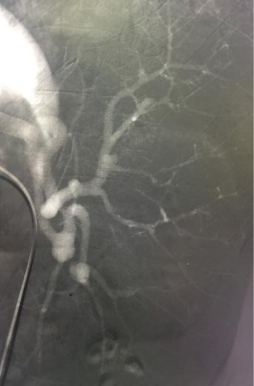

脾功能亢进是肝硬化最常见并发症,脾脏肿大,血细胞过分漪留脾脏内,使其破坏增多,导致白细胞明显下降易致感染,红细胞下降致贫血,血小板明显下降易致出血。 脾脏又是免疫器官。选择性脾动脉栓塞后,部分脾实质缺血性梗死、液化、机化、萎缩、纤维结缔组织增生,使脾脏缩小,削弱脾脏破坏血细胞的能力,使外周血细胞回升,纠正脾亢,同时保留其免疫功能(见图2,栓塞后脾脏造影)。

此外,脾动脉栓塞术(PSE)术后栓塞的脾动脉血流阻力增加,血流变缓,流量大量减少,脾静脉压力下降明显。门静脉高压致脾功能亢进,脾静脉血流量大为增加,可占门静脉血流量70%。PSE术后随着脾静脉血流量下降,门静脉血流量也大幅下降,门静脉高压得以缓解。门静脉压力下降,进而使胃冠状静脉、胃短静脉返流减少,从而降低肝硬化患者食管胃底静脉曲张破裂出血的风险,预防再出血,改善生存质量。

该患者在我院放射科接受经股动脉穿刺入路行脾动脉及脾动脉瘤栓塞术治疗(见图2),术后第二天即可下床活动,大腿根部只有约2毫米的穿刺点。1周后出院复查血常规白细胞数:5.4*109/L(正常值为3.5-9.5*109/L),血小板数55.0*109/L(正常值为100-300*109/L)。经过介入栓塞治疗,不仅解决了脾脏功能亢进的问题,而且小炸弹顺利拆除。此外,还一定程度上缓解了门静脉压力,预防上消化道再出血,可谓是“一箭三雕”之效。